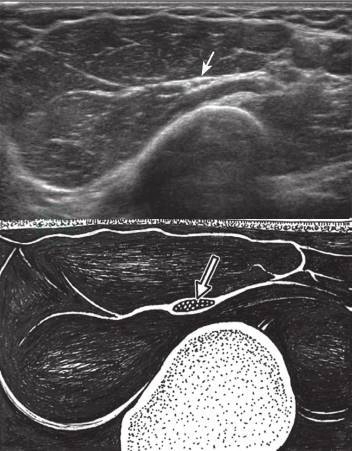

1.坐骨结节处

探头横切放置在坐骨结节和股骨大转子之间,可见坐骨神经横切面呈筛网状椭圆形结构(图10-28),自此可分别向上和向下追踪探查。横切面检查结束后,探头旋转90°可进行纵切面检查(图10-29)。

图10-28 坐骨神经短轴声像图

横切面于坐骨结节和股骨大转子之间显示坐骨神经GM:臀大肌;QF:股方肌;箭:坐骨神经

图10-29 坐骨神经长轴声像图

GM:臀大肌;QF:股方肌;箭:坐骨神经